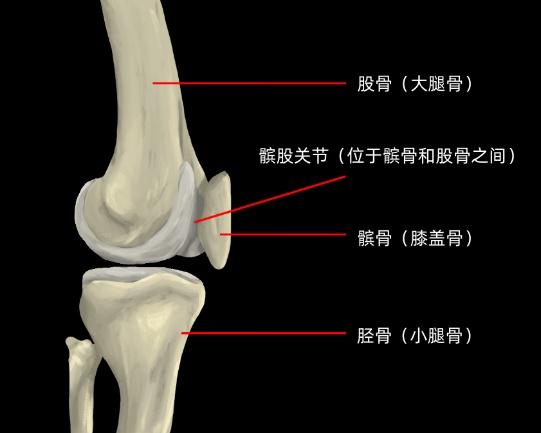

髌股关节由髌骨后表面和股骨髁间窝构成,其稳定性主要依赖于髌骨与股骨髁间窝的契合度。当人体进行屈膝、伸膝等动作时,髌骨会在股骨髁间窝中上下滑动。谢医师解释说,PFPS的发病原因可能包括膝关节的过度使用、髌骨的异常轨迹等。例如,频繁参与跑步、跳跃等运动会对膝关节产生重复性压力,而髋、膝周围肌肉力量不平衡和下肢力线不正常则可能导致髌骨轨迹异常,增加髌股关节的压力,从而损伤膝关节软组织。